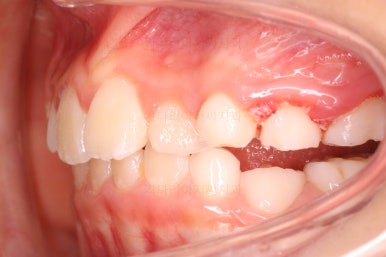

우선 처음 내원 하셨을 때의 입안의 상태를 보겠습니다.

아직 나이가 어리다 보니 곳곳에 유치가 남아 있었어요. 보통 이렇게 영구치가 다 나오지 않았을 경우, 보호자분들은 "치아교정"에 대해서는 전혀 생각해 보시지 않으셨을 수 있어요.

이번 환자분의 경우도 앞니가 거꾸로 물리는 상황이어서 치료가 필요한 상황이였습니다.